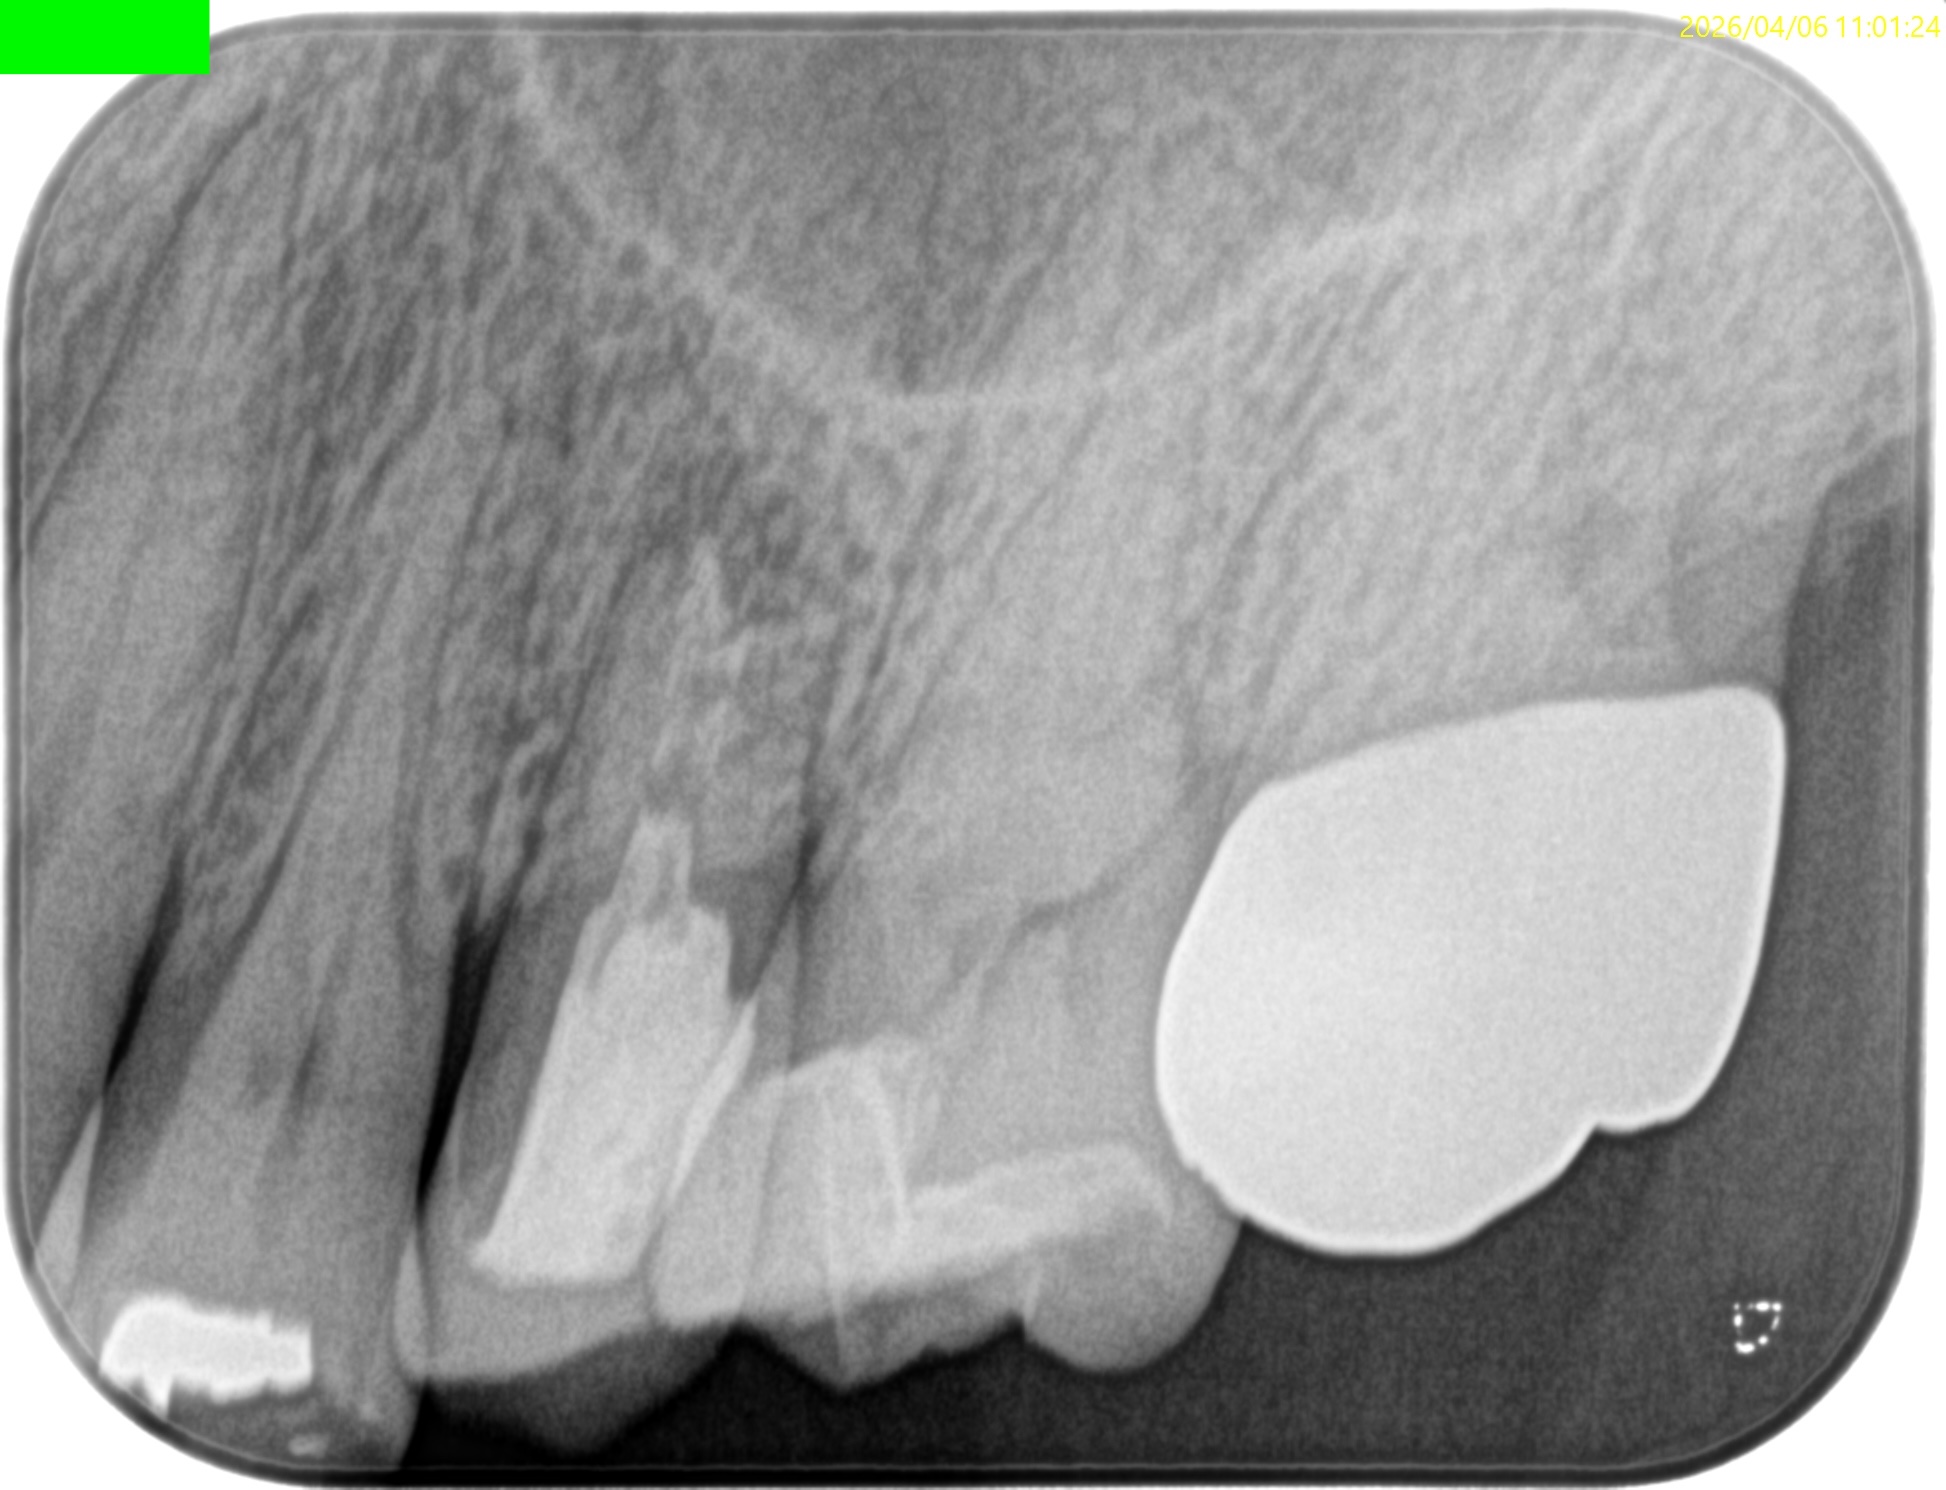

Pre-op Endo test(2026.4.6)

臨床症状はないが…

上顎洞炎は治癒したままだが、Lid TechniqueのLidごと材料が外れてしまっている。